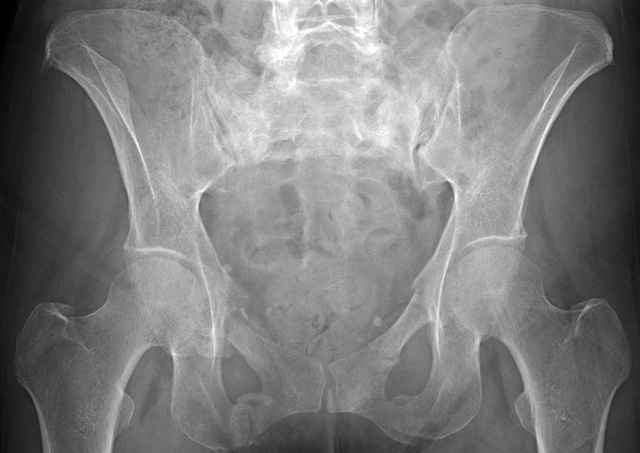

Initial Films

?Instability on Exam - Limited by Pain

NonOp Initial Mgmt